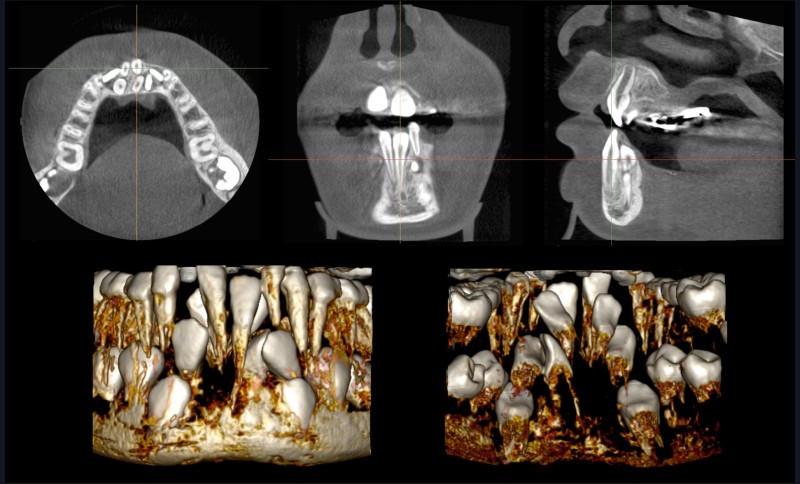

Nous suivons en orthodontie à l’hôpital de la Pitié-Salpêtrière une patiente de 9 ans qui présente un retard d’éruption dentaire inexpliqué à la mandibule : en bouche, la seule dent permanente du secteur incisivo-canin est la 41. La radiographie panoramique laisse suspecter la présence de germes surnuméraires. Une imagerie CBCT est prescrite et analysée classiquement via les vues multiplanaires (MPR) et les reconstructions volumiques basées sur des seuillages de niveau de gris (fig. 1).

L’analyse de l’imagerie CBCT est rendue difficile par le nombre important de dents surnuméraires présentes dans le secteur incisivo-canin mandibulaire. En particulier, la reconstruction volumique ne permet pas d’appréhender finement la position des différentes dents et de leurs racines. Cela complique l’établissement du plan de traitement, devant établir quelles sont les dents à avulser et celles à tracter avec un appareillage orthodontique. Cette décision de traitement serait grandement facilitée par des informations tridimensionnelles supplémentaires sur la forme des différentes dents, leur position tridimensionnelle ou encore leur édification radiculaire.